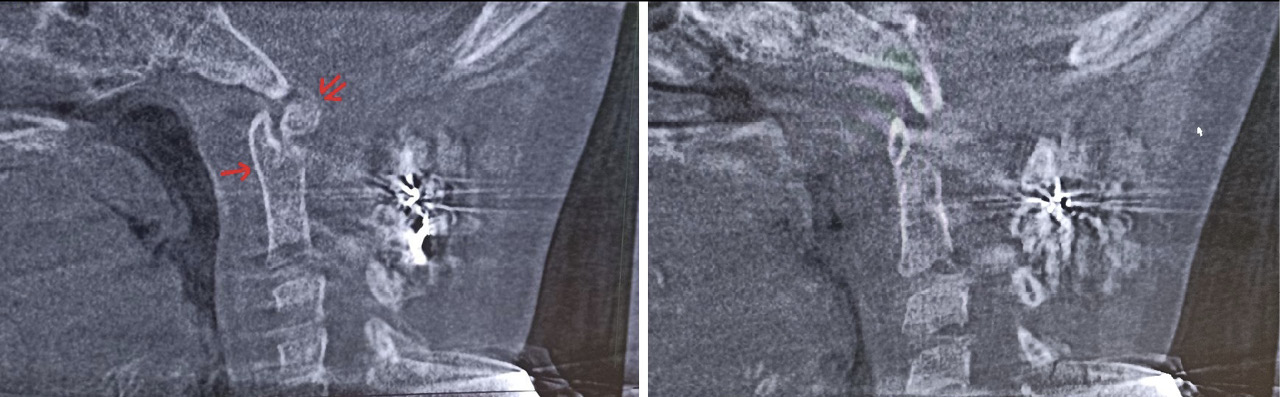

Пациентка Е. 9 лет обратилась на прием с жалобами на ограничение поворотов головой. Со слов матери, в мае 2018 г. ребенку проводилось оперативное лечение по поводу травмы шейного отдела позвоночника. Медицинские заключения не были предоставлены. При осмотре ребенок с синдромом Дауна. Голова по средней линии, пальпация области шейного отдела позвоночника безболезненна, объем пассивных и активных наклонов головы соответствовал нормативным значениям. При этом амплитуда пассивных и активных ротационных движений в шейном отделе позвоночника составила 15° и 20º в каждую сторону соответственно. При последующем ортопедическом осмотре было выявлено нарушение осанки по типу «сутулая спина» по Штаффелю. По данным анализа представленного диска с результатами ранее проведенной мультиспиральной компьютерной томографии шейного отдела позвоночника (дата исследования – май 2018 г.) был выявлен перелом зубовидного отростка С2 позвонка типа 1 по классификации L. D. Anderson и R.T. D'Alonzo, со смещением верхушки зубовидного отростка кпереди [9]. Плоскость перелома зубовидного отростка аксиса косая, края отломков неровные, нечеткие, диастаз между отломками неравномерный (рис. 5).

Рис. 5. Компьютерная томография шейного отдела позвоночника, сагиттальный срез (А), фронтальный срез на уровне зубовидного отростка С2 позвонка (Б). Стрелкой обозначено место перелома зубовидного отростка С2 позвонка

Для оценки ситуации в динамике была проведена КЛКТ, на которой на фоне динамической нерезкости (ребенок был неусидчив) и артефактов от металлоконструкции было отмечено следующее: суставные рентгеновские щели в латеральных атлантоаксиальных суставах: справа – не прослеживается, слева – неравномерно сужена до 0,4 мм в наиболее узком месте (рис. 6). Рентгеновская щель срединного атлантоаксиального сустава в сагиттальной плоскости не прослеживается (рис. 7А), в парасагиттальной плоскости – прослеживается, неравномерная (рис. 7Б). Зубовидный отросток С2 позвонка визуализируется в виде 2 фрагментов, дистальный из которых вместе с передней дужкой С1 позвонка представлен в виде не полностью слитного костного образования. Проксимальный фрагмент, лоцирующийся в проекции верхушки зубовидного отростка С2 позвонка, представлен в виде свободно лежащего отломка с неравномерно склерозированным контуром в проекции диастаза (см. рис. 7). Данная рентгенологическая картина соответствует состоянию после оперативного лечения по поводу травмы шейного отдела позвоночника со стабилизацией металлоостеосинтезом С1–С2 позвонков. Неправильно сросшийся перелом зубовидного отростка С2 позвонка. Частичный анкилоз срединного атлантоаксиального сустава и полный анкилоз правого латерального атлантоаксиального сустава.

Рис. 7. Конусно-лучевая компьютерная томография краниовертебральной области, сагиттальный срез (А), парасагиттальный срез (Б). Стрелкой отмечено место анкилоза срединного атлантоаксиального сустава. Двойной стрелкой обозначен свободно лежащий апикальный костный фрагмент зубовидного отростка аксиса